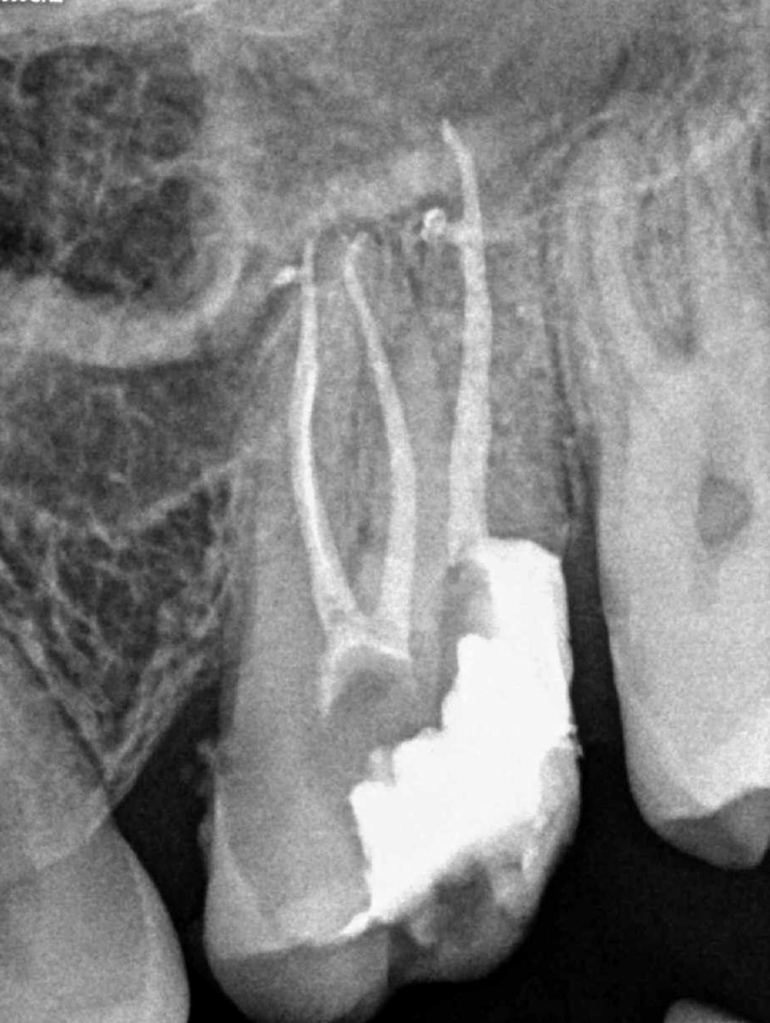

Molar inferior, conducto CM

Molar inferior, conducto MC, Reeco prendo